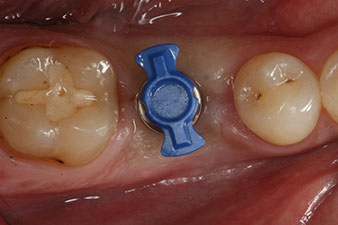

Въртящият момент, използван за машинно-задвижвано поставяне, е 43 Ncm. Освен това, след завинтване на измервателния щифт (SmartPeg), специално пригоден за импланта, стойността на ISQ се измерва със сондата на W&H Osstell ISQ модула.

Този модул е допълнителна екстра към Implantmed на W&H и е закачен към имплантологичния мотор (виж фиг. 11). Липсата на ISQ стойност непосредствено след поставянето е 64 оровестибуларно и 68 мезиодистално (максимална стойност = 100).

Тези стойности могат да показват отворено лечение или дори имедиатно възстановяване. Поради недостатъчния обем на кресталната кост при импланта, областта е подсилена с костните частици, събрани по време на препарацията на имплантното ложе и зашити, за да се изолира слюнката.

След зарастване на меките тъкани, стабилността на импланта е измерена отново преди протетичното възстановяване.

И двете стойности са практически непроменени и са между средния и високия диапазон, където по-ниската стойност винаги се използва като референтна стойност, която определя лечението.

Следователно, успешната остеоинтеграция и адекватната биологична стабилност могат да бъдат записани, което даде възможност да се вземе отпечатък в една и съща сесия.